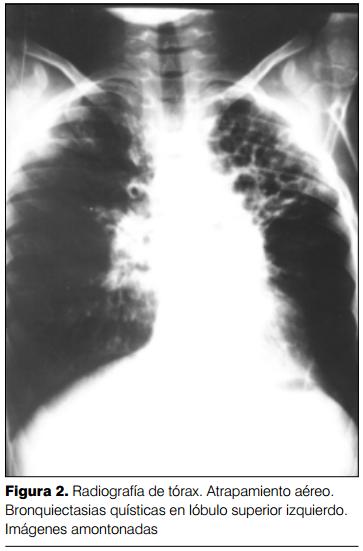

Del análisis de 394 radiografías se confirmaron los criterios de Woodring y colaboradores (8) y se agregaron otros: reticulado alveolar, aproximación del intersticio peribroncovascular ("imágenes amontonadas") (Fraser y Paré, 1979) (15) y panalización (figuras 1 y 2).

Las anormalidades específicas encontradas fueron: dilataciones cilíndricas, varicososaculares y quísticas (100%), engrosamiento del intersticio peribronquial (70%), atelectasia lobar o segmentaria (66%), atrapamiento aéreo (39%), oligohemia en mosaico (34%), hiperinsuflación compensadora (21%) y panalización (2%) (figuras 3 y 4).